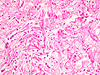

Paciente sexo masculino, de 17 anos, branco, com quadro clínico de forte emagrecimento e massa tumoral destrutiva óssea mandibular, volumosa de crescimento rápido.

Paciente de 12 anos, masculino com lesão expansiva, de crescimento lento em maxila E.

Paciente 19 anos, com lesão de crescimento lento e progressivo, deformante da mandíbula. Realizada hemi-mandibulectomia. A radiografia mostrada é referente à peça cirúrgica.